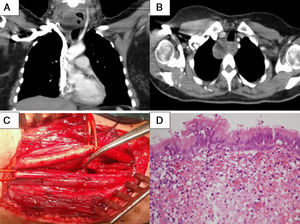

A y B) Imagen en TAC de masa quística cervical derecha con nivel hidroaéreo en su interior. C) Imagen operatoria, con vena yugular interna y arteria carótida externa disecadas, y cápsula del quiste broncogénico traccionado con pinza de Adson. D) Epitelio de tipo respiratorio tapizando la superficie del quiste (H&E 40×).

Exámenes complementarios: la ecografía cervical confirmó la presencia de una masa cervical derecha, heterogénea, e imagen en probable relación con presencia de aire en su interior. La tomografía axial computarizada (TAC), corroboró la existencia de una masa de partes blandas de 8cm de diámetro mayor, localizada en encrucijada cervicotorácica, por debajo del hemitiroides derecho, independiente del mismo, con contenido aéreo en su interior (fig. 1A y B).

Tras instauración de tratamiento antibiótico de amplio espectro, y desaparición de la sintomatología general y loco-regional, la paciente fue intervenida quirúrgicamente a través de cervicotomía lateral derecha, con hallazgos operatorios compatibles con la exploración y pruebas complementarias, siendo factible la exéresis completa del proceso (fig. 1C). La evolución hospitalaria posquirúrgica fue favorable desde el punto de vista clínico y radiológico, continuando asintomática y sin signos de recidiva en los controles radiológicos y endoscópicos, 6 meses después.

El estudio anatomopatológico reveló en la pared interna de la formación extirpada, revestimiento por epitelio respiratorio, cilíndrico, seudoestratificado y con células caliciformes, concluyendo el diagnóstico en quiste broncogénico (fig. 1D).